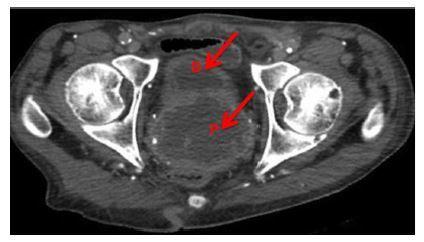

The urinary tract is an often forgotten and under-appreciated source of infection in anuric hemodialysis patients. Bladder abscess, also called pyocystis, is a severe complication of low urinary flow that can be difficult to detect, leading to delays in treatment and increased morbidity. The emergency physician should maintain a high suspicion for pyocystis, which can be quickly diagnosed by bedside ultrasound. We report a case of a hemodialysis patient with an initially minor presentation who developed sepsis secondary to pyocystis and prostate abscess.